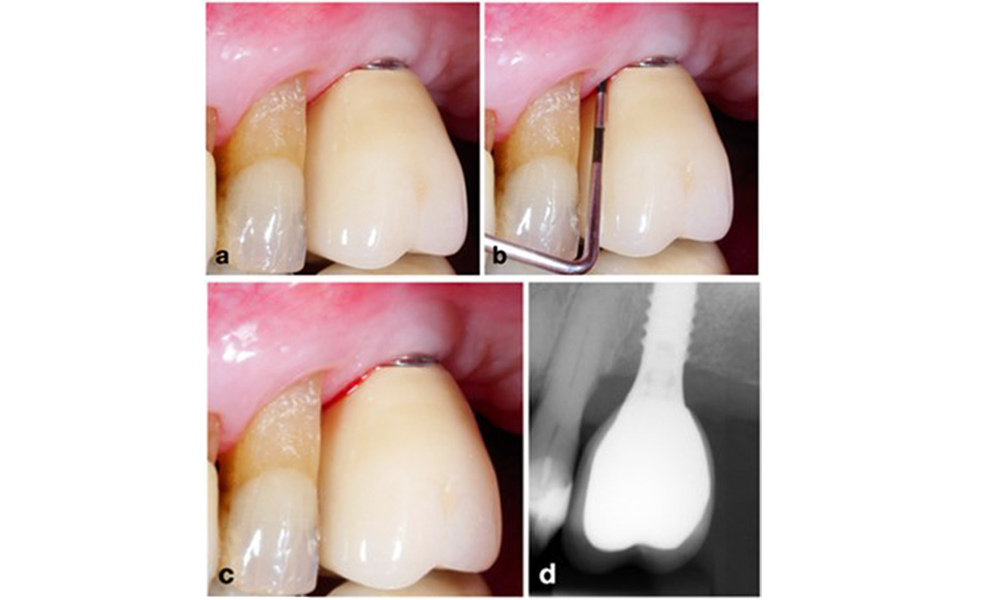

The World Workshop on the Classification of Periodontal and Peri‐Implant Diseases and Conditions from 2017 established diagnostic criteria for peri-implant mucositis and peri-implantitis (Renvert et al. 2018). Peri-implant mucositis is defined as (1) presence of inflammation around the implant (i.e., redness, swelling, line or drop of bleeding within 30 seconds of probing), combined with (2) no additional bone loss after initial healing (figure 1).

Implant in position 26 with peri-implant mucositis (a–c). The probing depth value of 5 mm (b) remains consistent with the measurement taken a few weeks after placing the prosthetic reconstruction. There is bleeding on probing (c) but the radiograph indicates no additional bone loss beyond what is expected for marginal bone remodelling (d).

Figure 1. Implant in position 26 with peri-implant mucositis (a–c). The probing depth value of 5 mm (b) remains consistent with the measurement taken a few weeks after placing the prosthetic reconstruction. There is bleeding on probing (c) but the radiograph indicates no additional bone loss beyond what is expected for marginal bone remodelling (d).